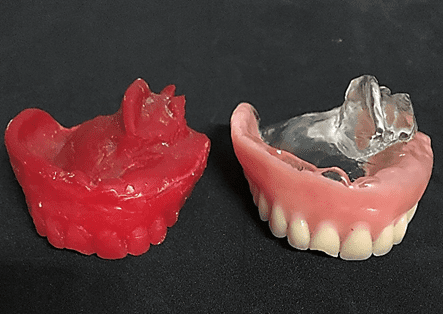

The treatment plan consisted of performing a total superior prosthesis obturator by the cloning technique and the preparation of a conventional removable partial prosthesis (PPR). Cloning of the total superior obturator prosthesis began with the application of solid vaseline on the bench and in the old prosthesis, the condensation silicone (Clonage®, Nova DFL, Brazil) was manipulated to model the inner part of the prosthesis, covering a portion of the outer edge, leaving it expulsive (figure 3).

Then, a thin layer of solid vaseline was inserted into the base already modeled and the cover and copy of the teeth were made (figures 4 and 5). Soon after, a base of the prosthesis was elaborated with acrylic resin (Duralay®, Reliance, USA) by the brush technique introducing the resin in small proportions, because this type of material has less polymerization contraction (figure 6). Then, perforations were made in the posterior region of each side of the cover, in order to fill the mold with wax 7 (figure 7). Where initially the wax was heated to boiling and with the aid of a glass dripper the increments were added by filling the mold completely (figure 8). And, after cooling the wax, the base cover silicone was removed, thus obtaining the properly mentioned cloning of the old prosthesis (figure 9).

Figure 9: Clone of the total obturator prosthesis.

Thus, because the patient already makes use of a shutter prosthesis, it is possible to choose to perform the cloning technique (DA CUNHA DINIZ et al., 2015), even though it was without adequate retention because it had passed the useful life of 3 years (ANTUNES et al., 2008), it was correctly constructed and restored adequate functional space. According to Gomes and Castro (2009) the technique consists in the realization of the silicone matrix, and the inclusion in muffle and for the duplication of teeth recommend fluid silicone, as it will prevent the formation of bubbles and irregularities. In this case, the technique underwent some modifications made by the authors to ensure greater agility to the procedure. The material of choice to obtain the replica of the base was the acrylic resin duralay, because it presents little polymerization contraction. As for the tooth region, it was made with wax 7, where in the next phase the teeth copied in wax were replaced by the stock teeth directly. The modifications showed a good cost-benefit ratio, not requiring the laboratory stage of acrylization in a conventional oven or microwave for the preparation of the clone.